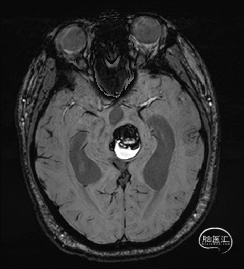

术前MRI检查

术前MRI检查提示左侧丘脑中脑海绵状血管瘤并卒中,梗阻性脑积水;

诊断:1.左侧丘脑中脑海绵状血管瘤并卒中,2.梗阻性脑积水;

年轻患者,较短时间内发生左侧丘脑二次出血,出现右侧面部及上肢麻木,复视,第二次出血后并发梗阻性脑积水,出现头痛。结合病史、神经系统体征、头颅CT及MRI检查,诊断左侧丘脑及中脑CM并卒中、脑积水明确,并导致了神经功能障碍,具备手术指征。

本例患者磁共振检查清晰显示病变位于左侧丘脑中脑区域,且位于丘脑内下方向中脑顶盖延续,病变的上部、前部、外侧部都有重要的神经组织,因此,手术从上方、前方、外侧方向切除病变均难以实施;